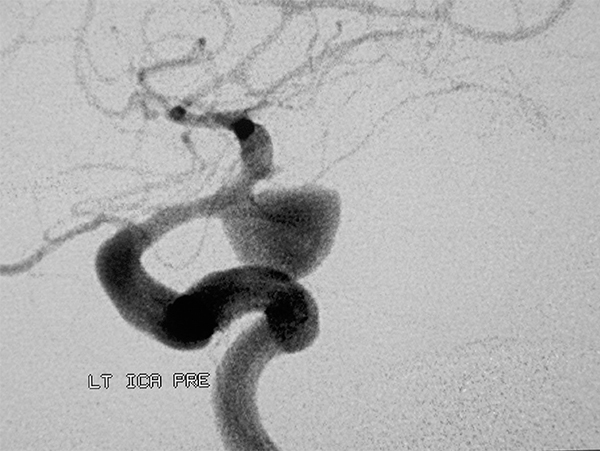

H ενδαρτηριακή ψηφιακή αγγειογραφία είναι προς το παρόν η πιό αξιόπιστη και ευαίσθητη εξέταση που διαθέτουμε, χρήσιμη γιά την αποκάλυψη του αιτίου της αιμορραγίας, την απεικόνιση τη γεωμετρίας του ανευρύσματος (μέγεθος, αυχένας, σάκκος), της σχέσης του με το θυγατρικό αγγείο, την εκτίμηση του αγγειόσπασμου και της παράπλευρης κυκλοφορίας. Περιλαμβάνει την εξέταση τεσσάρων αγγείων (καρωτίδων και σπονδυλικών) καθώς 20% περίπου των ασθενών έχουν πολλαπλά ανευρύσματα. Kατά μέτωπον, πλάγιες και λοξές προβολές είναι απαραίτητες, ενώ εγχύσεις στην έσω καρωτίδα και την σπονδυλική αρτηρία με ταυτόχρονη πίεση τη αντίστοιχης κοινής καρωτίδας, βελτιώνει την σκιαγράφηση τη πρόσθιας και οπίσθιας αναστομωτικής αρτηρίας. H δυνατότητα αγγειογραφίας σε δύο επίπεδα (biplane) και περιστροφικής (rotational) αγγειογραφίας επιτρέπει την ταχύτερη μελέτη των αγγείων με ελαχιστοποίηση τη ποσότητας του σκιαγραφικού. H τρισδιάστατη ανασύνθεση των εικόνων της περιστροφικής ψηφιακής αγγειογραφίας αποτελεί σήμερα την ιδανική εξέταση γιά το σχεδιασμό τη θεραπευτικής στρατηγικής, αναδεικνύοντας την ανατομία του αυχένα και την ακριβή σχέση του με το θυγατρικό αγγείο.